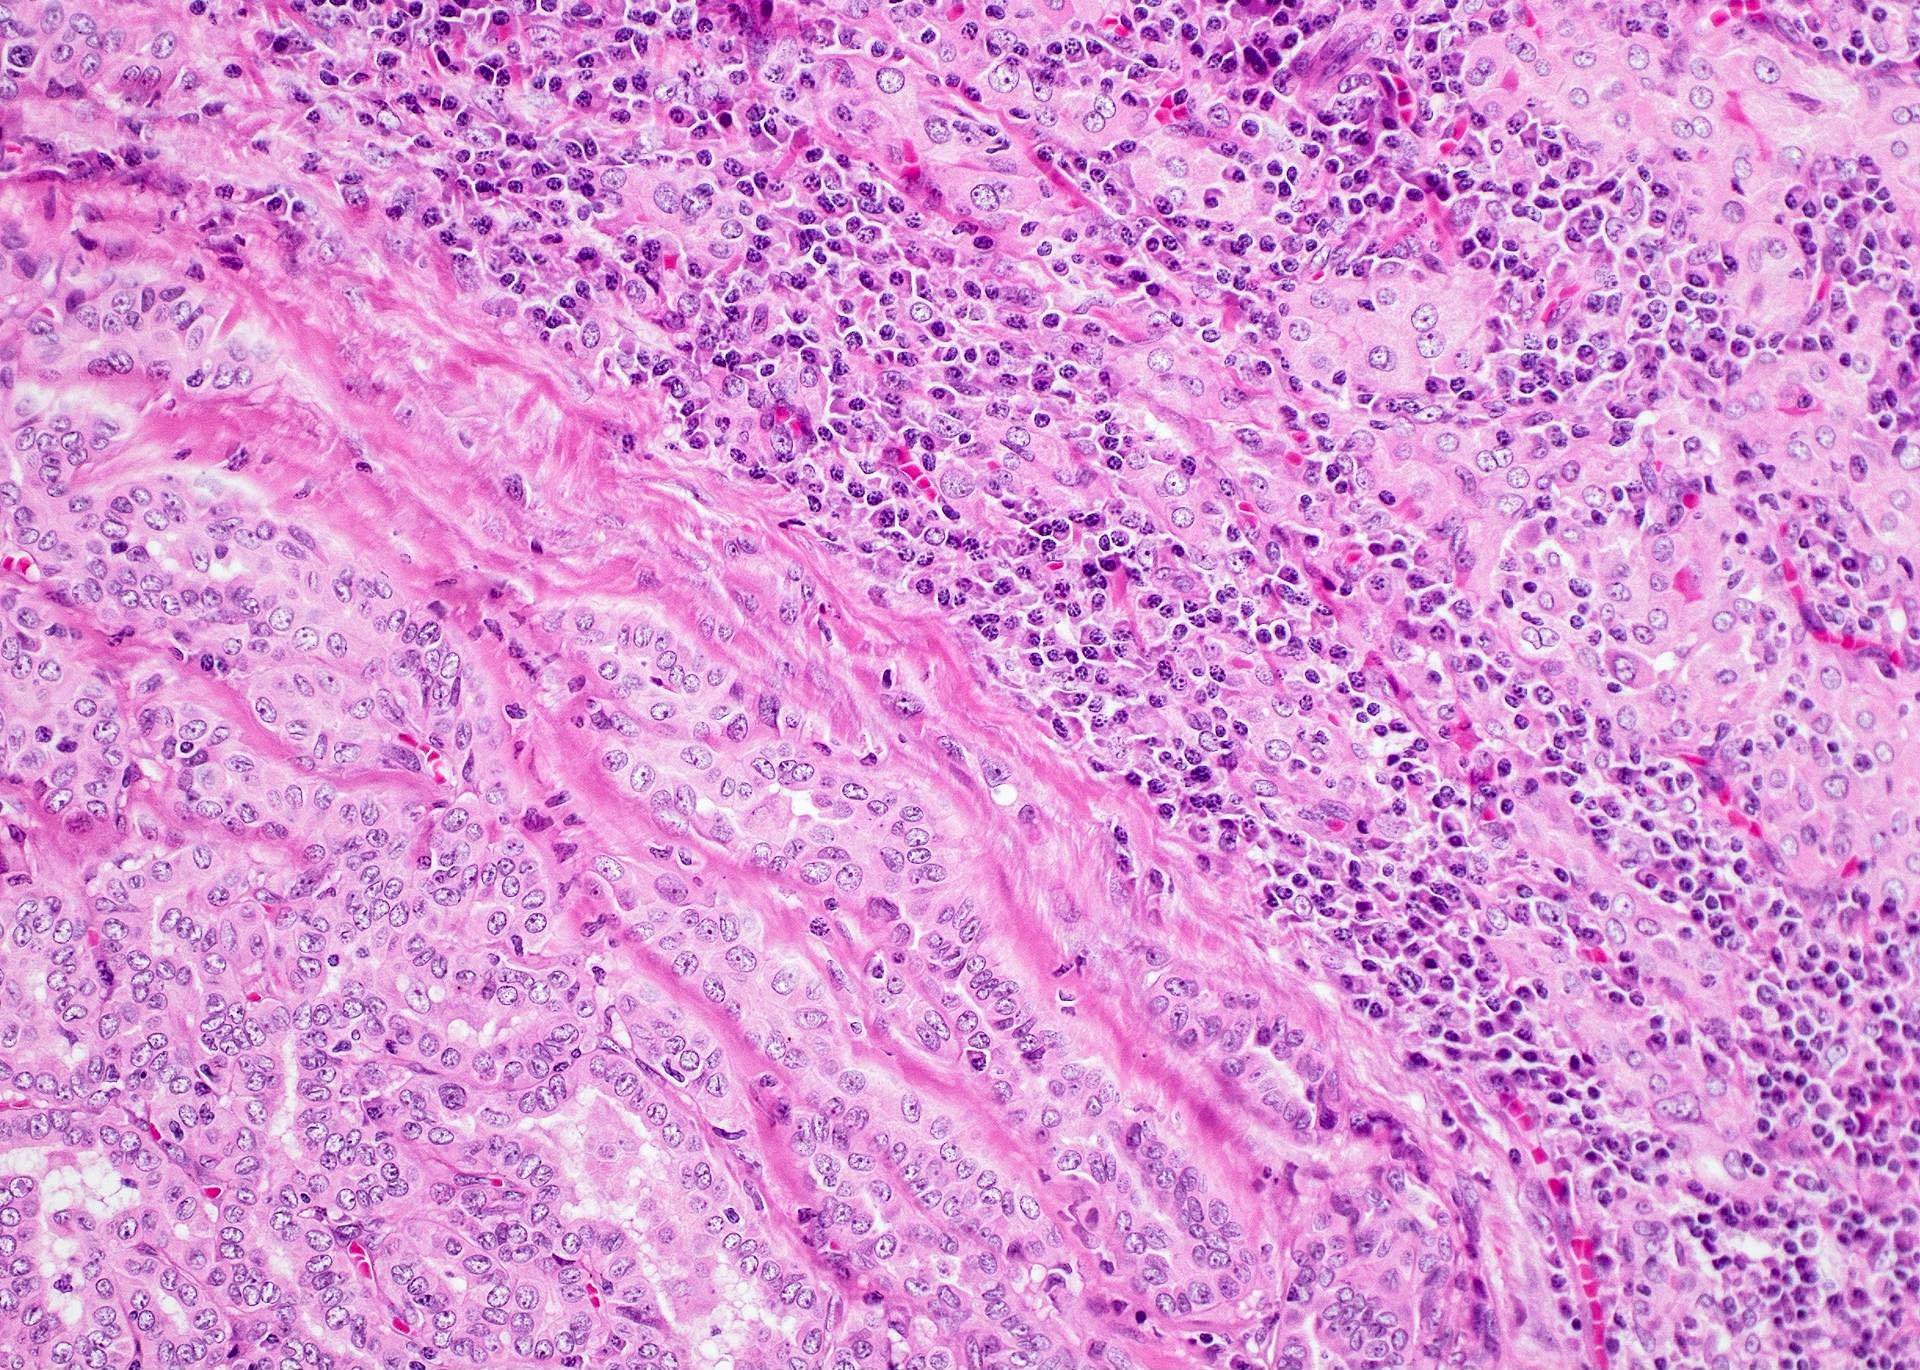

Microscopic (histologic) description

- Classic form: diffuse infiltration of thyroid parenchyma with lymphocytes and plasma cells; lymphoid follicle formation with germinal centers (Best Pract Res Clin Endocrinol Metab 2019;33:101367)

- Polymorphic lymphocytic infiltrate, predominantly T cells

- Thyroid follicular destruction

- Atrophic thyroid follicles; many lined by oncocytic cells / oncocytes having abundant granular eosinophilic cytoplasm; rarely squamous metaplasia

- Later fibrosis and nodularity (Virchows Arch 2013;462:557)

- Fibrous (or fibrosing) variant: extensive keloid-like fibrosis of thyroid parenchyma, fibrous septa divide the parenchyma into lobules, mononuclear cell infiltration, lymphoid follicles, thyroid follicular atrophy, oncocytic cell and squamous metaplasia (Autoimmun Rev 2014;13:391)

- IgG4 related variant: dense lymphoplasmacytic infiltrate, enriched in IgG4 producing plasma cells (> 20 cells per high power field); interstitial fibrosis; often associated with obliterative phlebitis (Autoimmun Rev 2014;13:391)

- Juvenile thyroiditis, Hashitoxicosis and painless thyroiditis: rare / absent germinal center formation and follicular atrophy, follicular cell hyperplasia, less pronounced oncocytic cell metaplasia and fibrosis (Autoimmun Rev 2014;13:391)

- Variable atypia of follicular cells and oncocytic cells, may mimic and act as a precursor (limited evidence) of papillary thyroid carcinoma (Endocr Pathol 2021;32:368)

- Squamous metaplasia of follicular epithelium can be confused with solid cell nests (J Clin Endocrinol Metab 2012;97:2209)

- May be associated with colloid goiter, follicular neoplasm, oncocytic cell neoplasm, papillary thyroid carcinoma and primary thyroid lymphoma (Acta Cytol 2009;53:507, Front Oncol 2017;7:53)

Microscopic (histologic) images

Contributed by Andrey Bychkov, M.D., Ph.D. and Shipra Agarwal, M.D.